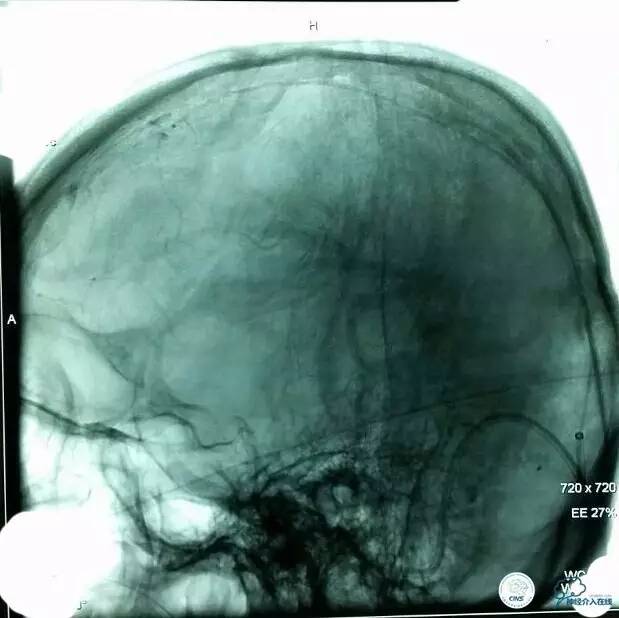

▼取栓后再次,微导管到矢状窦:

▼正位造影:

▼微管造影: